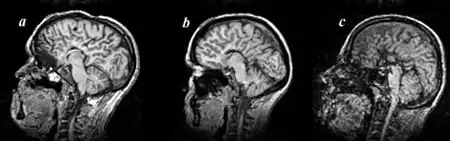

Agenesis of the corpus callosum (ACC) is a rare birth defect in which there is a complete or partial absence of the corpus callosum. It occurs when the development of the corpus callosum, the band of white matter connecting the two hemispheres in the brain, in the embryo is disrupted. The result of this is that the fibers that would otherwise form the corpus callosum are instead longitudinally oriented along the ipsilateral ventricular wall and form structures called Probst bundles.

In addition to agenesis, other degrees of callosal defects exist, including hypoplasia (underdevelopment or thinness), hypogenesis (partial agenesis) or dysgenesis (malformation).[1]

Callosal disorders can be diagnosed through brain imaging studies or during autopsy.[8] They may be diagnosed through an MRI, CT scan, Sonography, prenatal ultrasound, or prenatal MRI.[1]